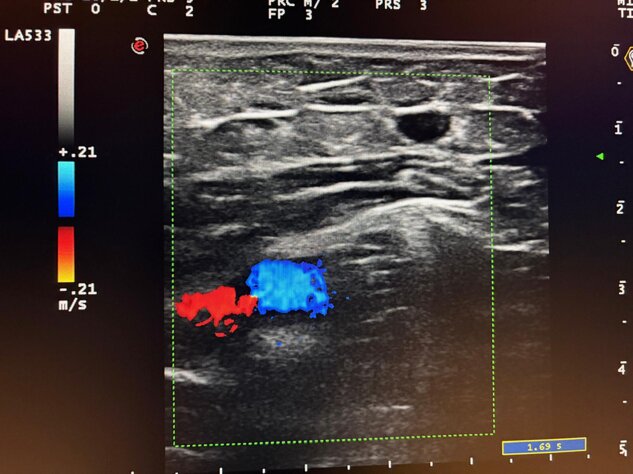

Ecocolordoppler

Incontinenza della valvola terminale della crosse safeno-femorale con reflusso venoso alla manovra di Valsalva.